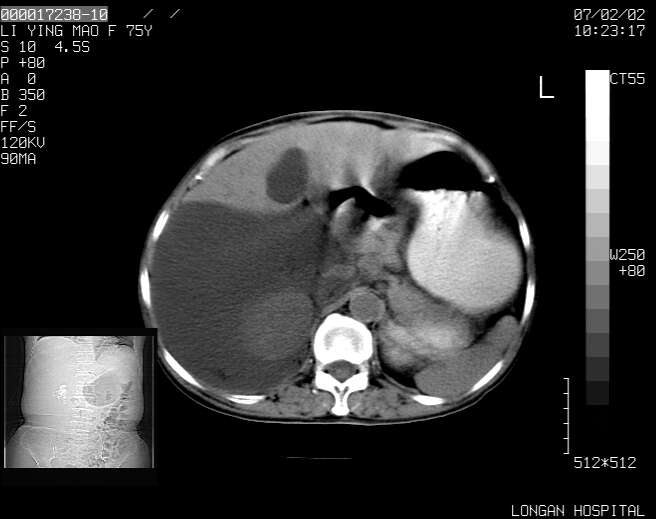

以下是引用dyqct在2007-2-10 8:53:00的发言:[br]考虑:1、肝脏多发囊肿[br] 2、左肾囊肿,右肾多发结石并积水。[br] 3、右胸少量积液。[br] 4、右肾周包裹性积液或淋巴管瘤(有见缝就钻的征象、薄隔、小结节状钙化)?[br] 5、腰椎动脉瘤样骨囊肿?[br] [br] [br]